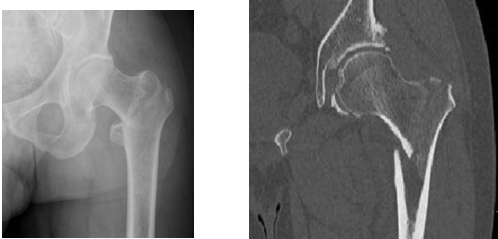

老年髋部骨折分为股骨颈骨折和粗隆间骨折又被称为“人生最后一次骨折”

股骨颈股则属于囊内骨折,不愈合和缺血坏死发病率高。

粗隆间骨折属于囊外骨折,很少影响股骨头供血,骨折部位为松质骨结构,血运丰富。因此,与股骨颈骨折不同,粗隆间骨折发生骨不连和股骨头坏死的概率很低。

一 股骨颈骨折的手术治疗首选人工股骨头置换

二 股骨粗隆间骨折的治疗首选股骨近端髓内钉固定(PFNA/Intertan)